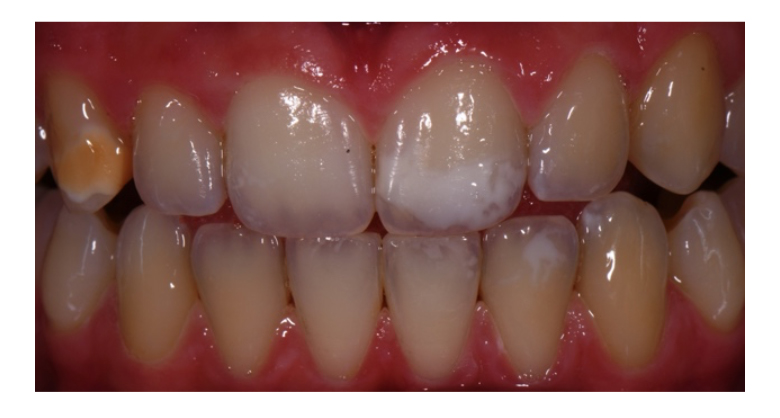

Durante l’esame obiettivo con l’ausilio di una reflex per macrofotografia odontoiatrica, individuiamo delle white spot lesions (WSL) da MIH sui denti 2.1, 3.2, 3.6 e 4.6 classificate ICDAS-II di tipo 2 e una brown spot lesions (BSL) da amelogenesi imperfetta (AI) sul dente 1.3 (fig. 1).

Dalla documentazione presente in cartella si evidenzia che queste lesioni erano già presenti anche prima del trattamento ortodontico.

Da un esame più approfondito osserviamo che la WSL sul dente 2.1 presenta due lesioni sovrapposte, una superficiale di tipo WSLs dovuta alla terapia ortodontica e una profonda da MIH. Quest’ultima come anche la lesione del dente 3.2 risultano progredire positivamente verso la superfice dello smalto rendendosi idonee ad un trattamento combinato per WSL. Le condividiamo con la paziente che a questo punto ci comunica il suo disagio dovuto a queste “macchie bianche” e la presenza di sensibilità dentinale.